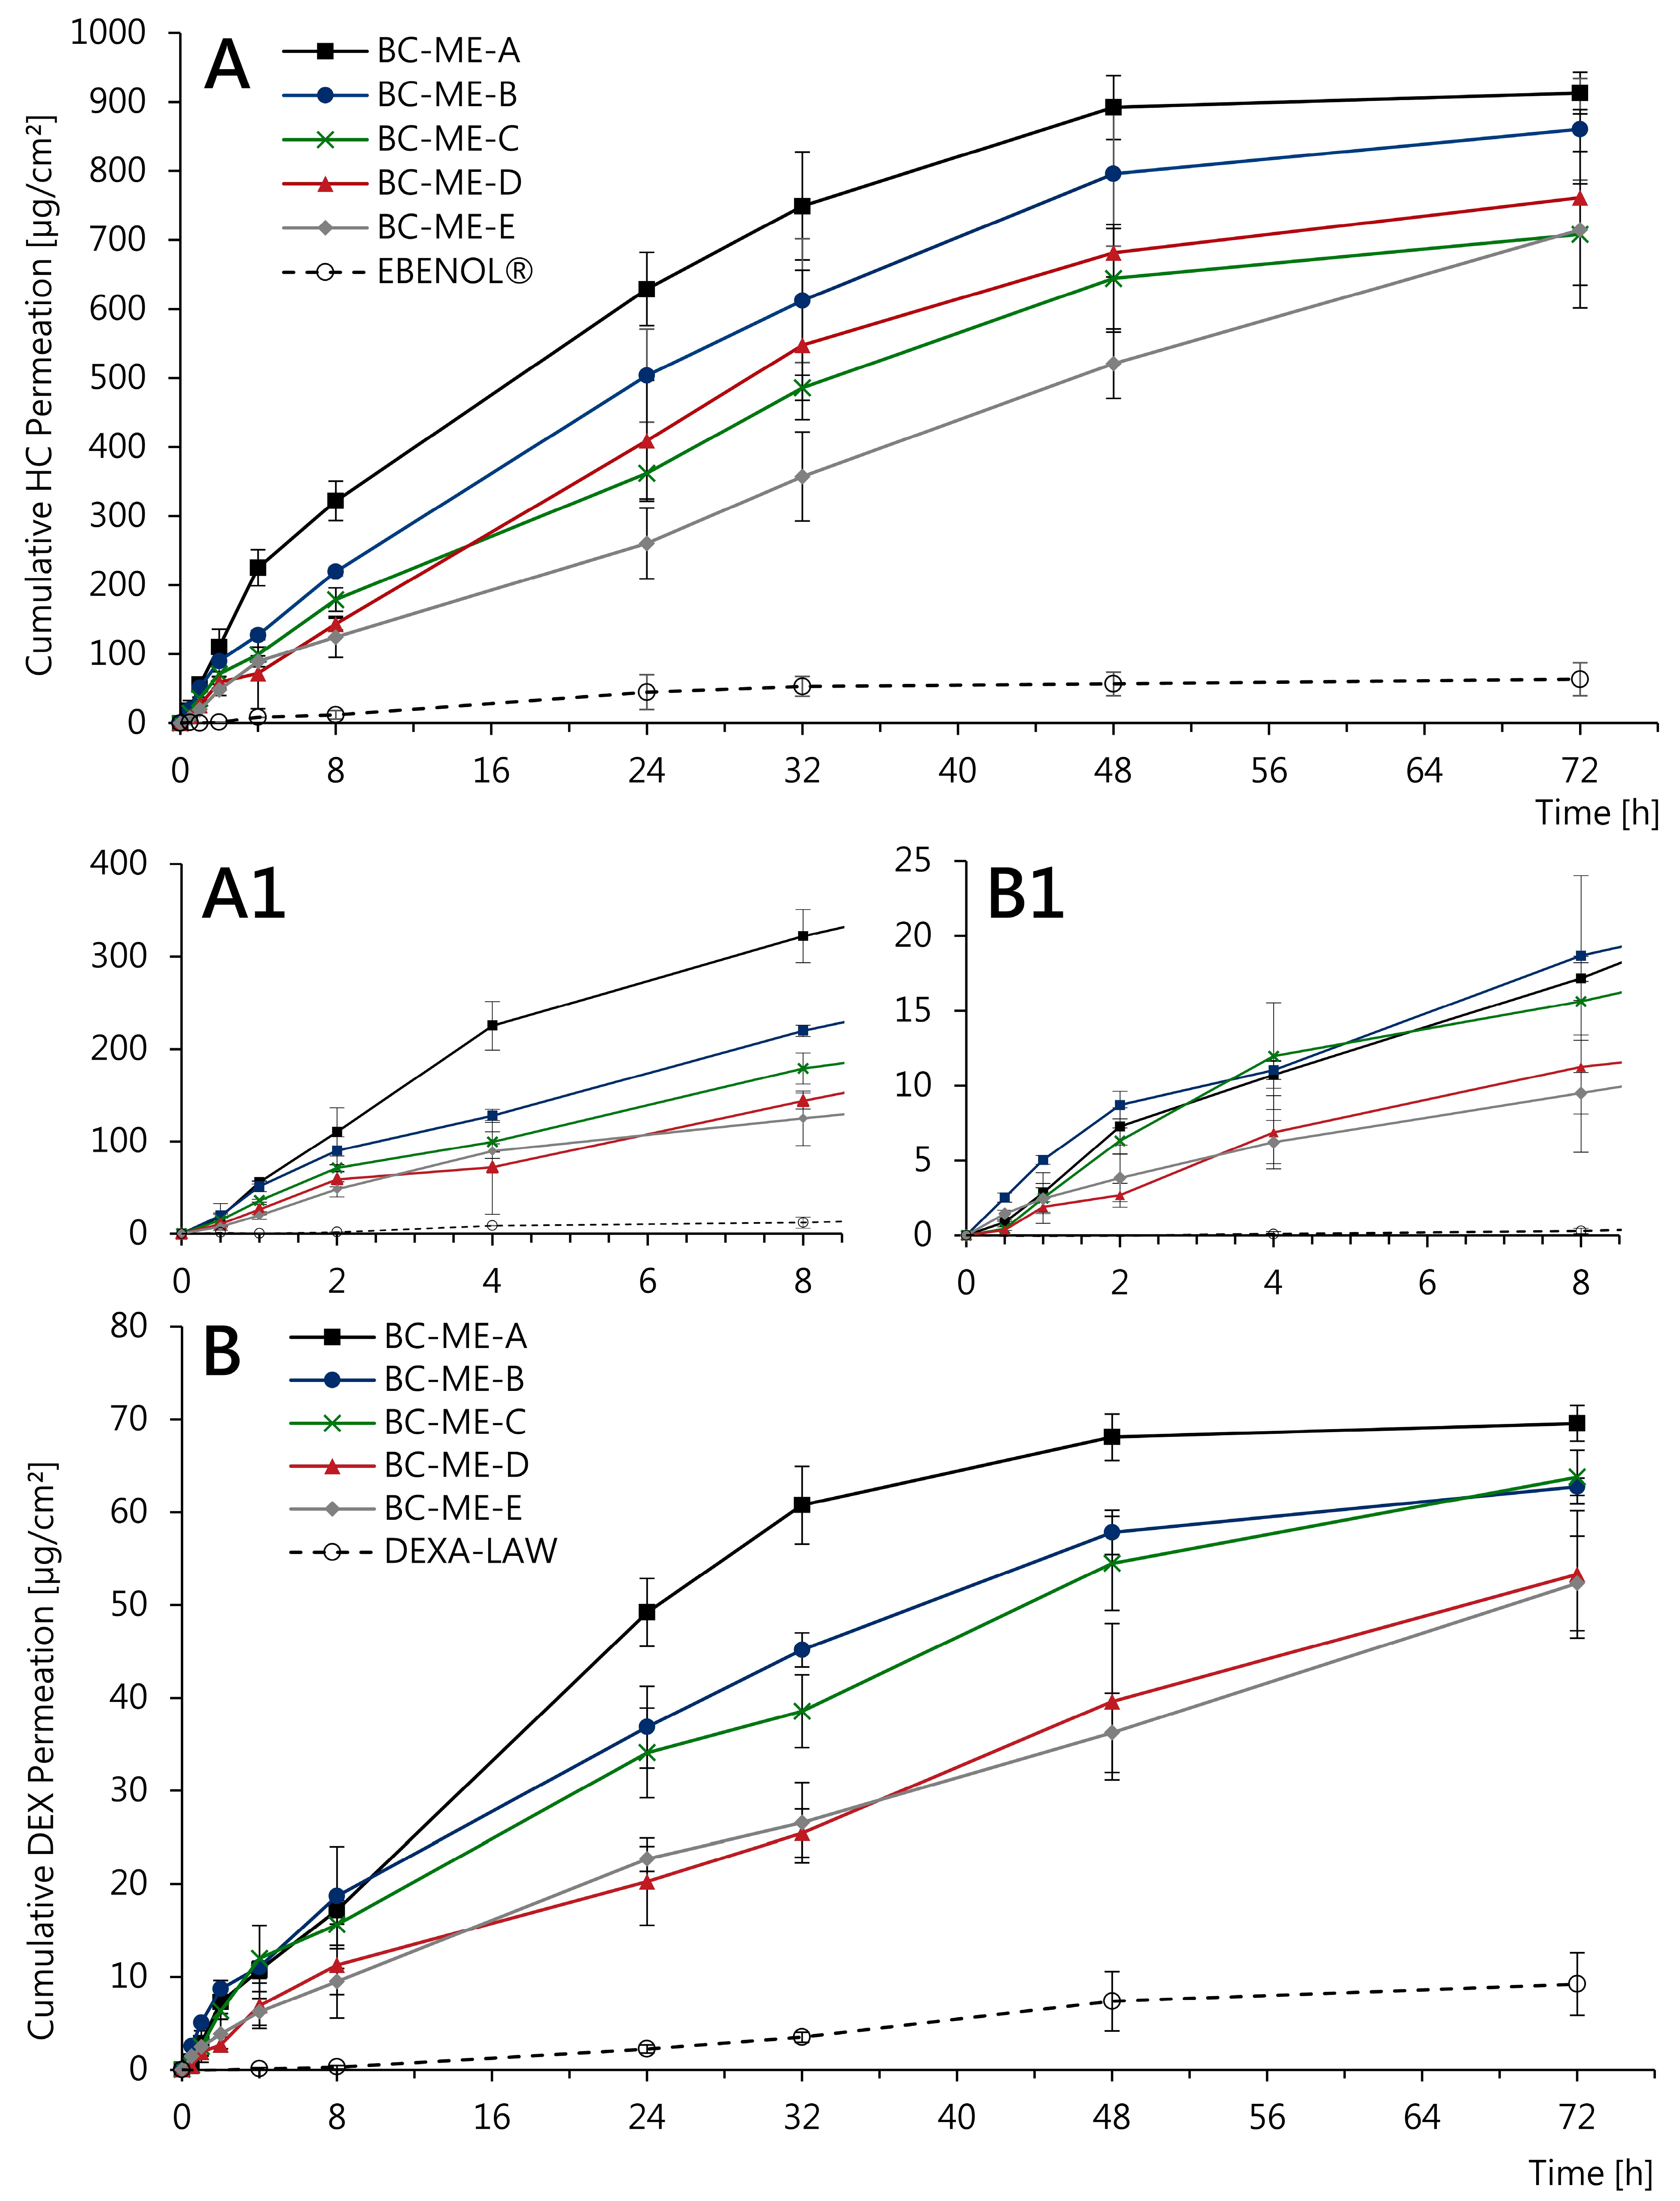

3.3.4. In Vitro Permeation